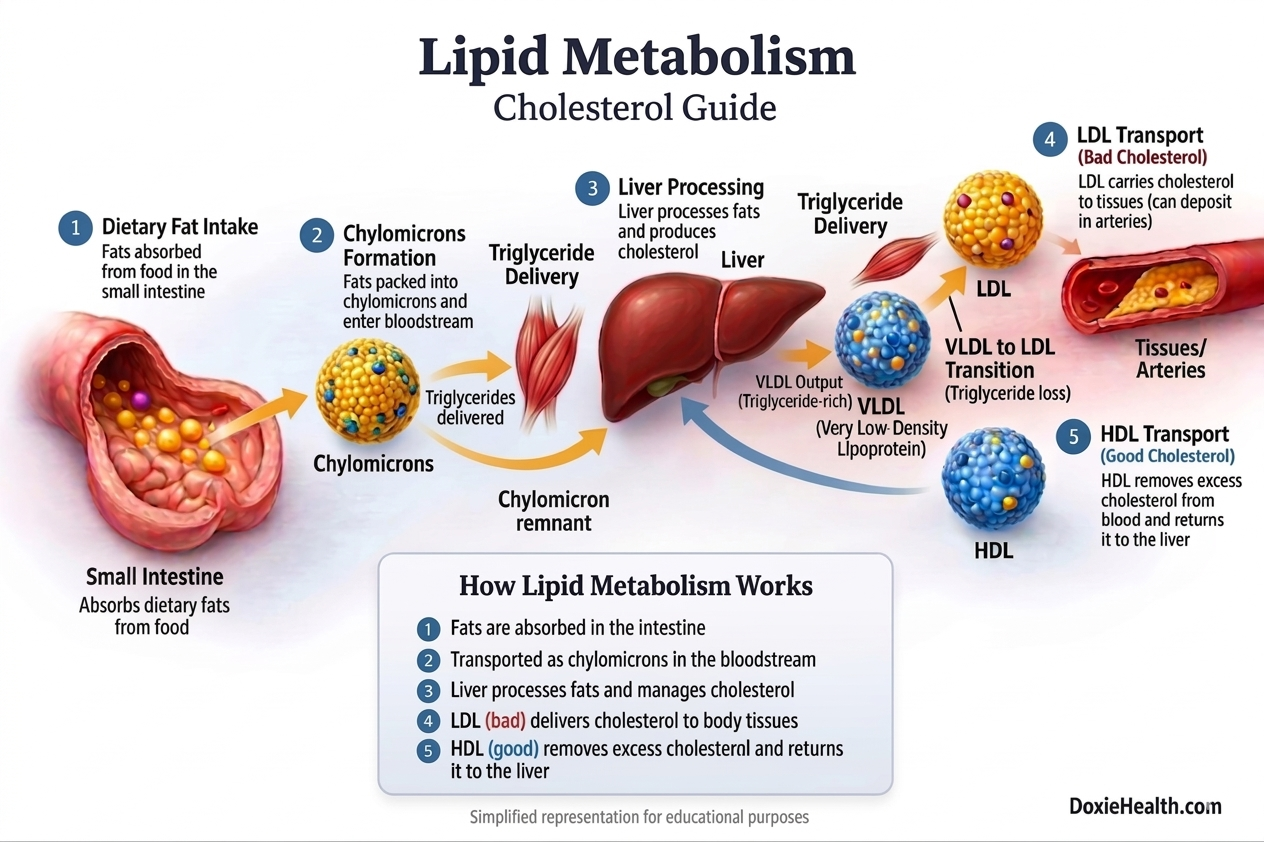

Lipid Metabolism — How Fats Travel in Your Body

After a meal, your small intestine absorbs dietary fats. However, these fats cannot be used directly by the body. They must first be digested, packaged, and transported so they can either be used for energy or stored for later use.

Because lipids are not water-soluble, they cannot travel freely in the bloodstream. To solve this, the body uses specialized “transport particles” called lipoproteins (lipid+Protein) to carry triglycerides and cholesterol through the blood.

Each type of lipoprotein has a specific role:

- Chylomicrons → carry dietary fats (Mainly triglycerides) from the small intestine to the body

- VLDL → LDL → deliver triglycerides and cholesterol to the body

- HDL → removes excess cholesterol from blood stream and returns it to the liver

Let’s understand this step by step in a simple way.

Absorption from the Small Intestine

After digestion, fats are absorbed in the small intestine. These fats are mainly in the form of triglycerides, along with a small amount of cholesterol.

Since fats cannot travel freely in the blood, the body packages them into tiny particles called chylomicrons, which enter the bloodstream through the lymphatic system.

These act as the first transport vehicles carrying fats from your diet.

Delivery of Energy to Tissues

Chylomicrons travel through the bloodstream and deliver triglycerides (energy) to:

- Muscles (for immediate use)

- Fat tissue/adipose tissue (for storage)

After delivering most of their triglycerides, the remaining particles (called chylomicron remnants) are taken up by the liver.

The Liver — The Central Processing Unit

The liver plays a central role in lipid metabolism. Nearly 80% of the cholesterol in the body is produced by the liver, while the remaining portion comes from the diet.

Along with producing cholesterol, the liver also repackages fats into VLDL (Very Low-Density Lipoprotein).

These particles primarily carry triglycerides, along with a smaller amount of cholesterol, into the bloodstream.

From VLDL to LDL

As VLDL circulates, it delivers triglycerides to tissues. As it loses these triglycerides, it gradually transforms into LDL (Low-Density Lipoprotein).

LDL is richer in cholesterol and primarily delivers it to body cells.

HDL — The Cleanup System

To balance this, the body uses HDL (High-Density Lipoprotein).

HDL collects excess cholesterol from the bloodstream and transports it back to the liver for removal. This protective process is known as reverse cholesterol transport.

| Simple Takeaway VLDL, LDL, and HDL are lipoproteins — transporters that carry lipids (triglycerides and cholesterol) in the blood. LDL delivers cholesterol outward. HDL brings it back. The balance between the two determines your long-term cardiovascular risk. |